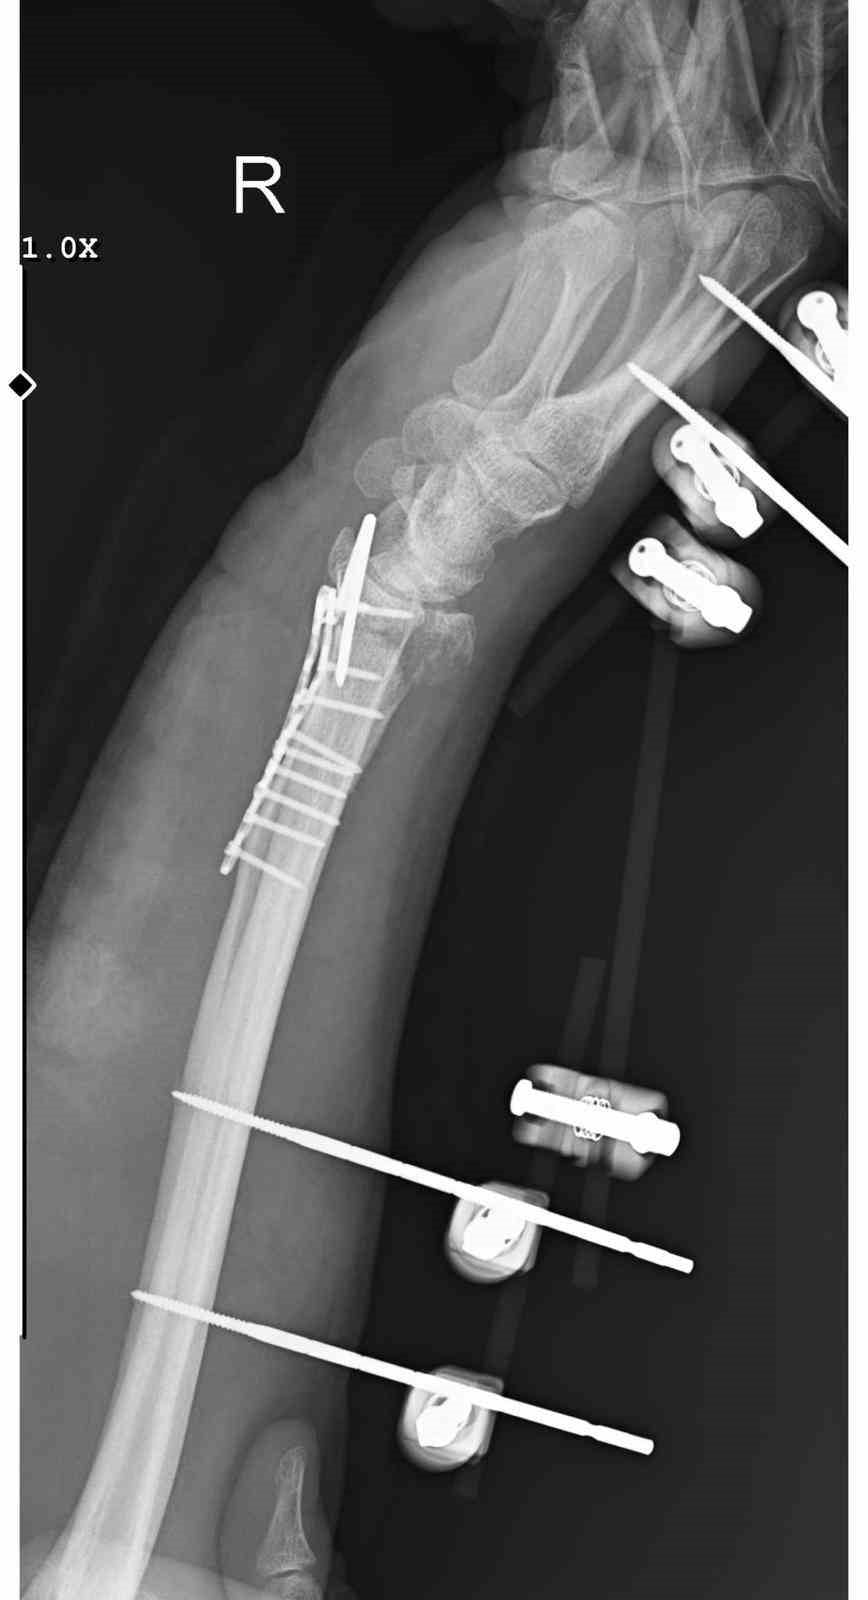

Arslantaş'ın geçirdiği ameliyat yaklaşık 3 saat sürdü; bilek kemiğine 11 adet platin takıldı ve üzerindeki yara dolayısıyla 15 dikiş atıldı. Hastaneden verilen bilgilere göre, iki ay boyunca kolunun sabit kalacağı, ardından yaklaşık 2,5 ay sürecek fizik tedavi programı uygulanacağı belirtildi. Doktorlar, hastanın his ve hareket kaybı riskiyle karşı karşıya olduğunu ifade etti.